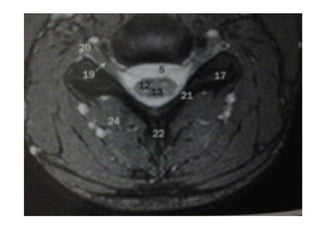

On transverse images MS lesions typically have a round or triangular shape and are located

posteriorly or laterally